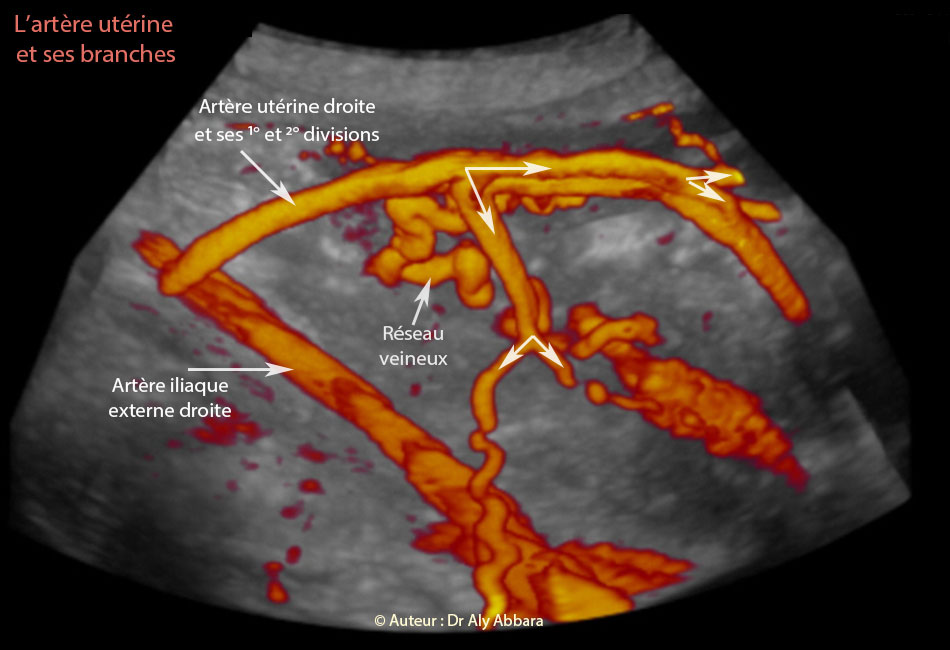

Image échographique animée en 3D montrant les branches de la première et la deuxième divisions de l'artère utérine droite

Auteur : Dr Aly Abbara